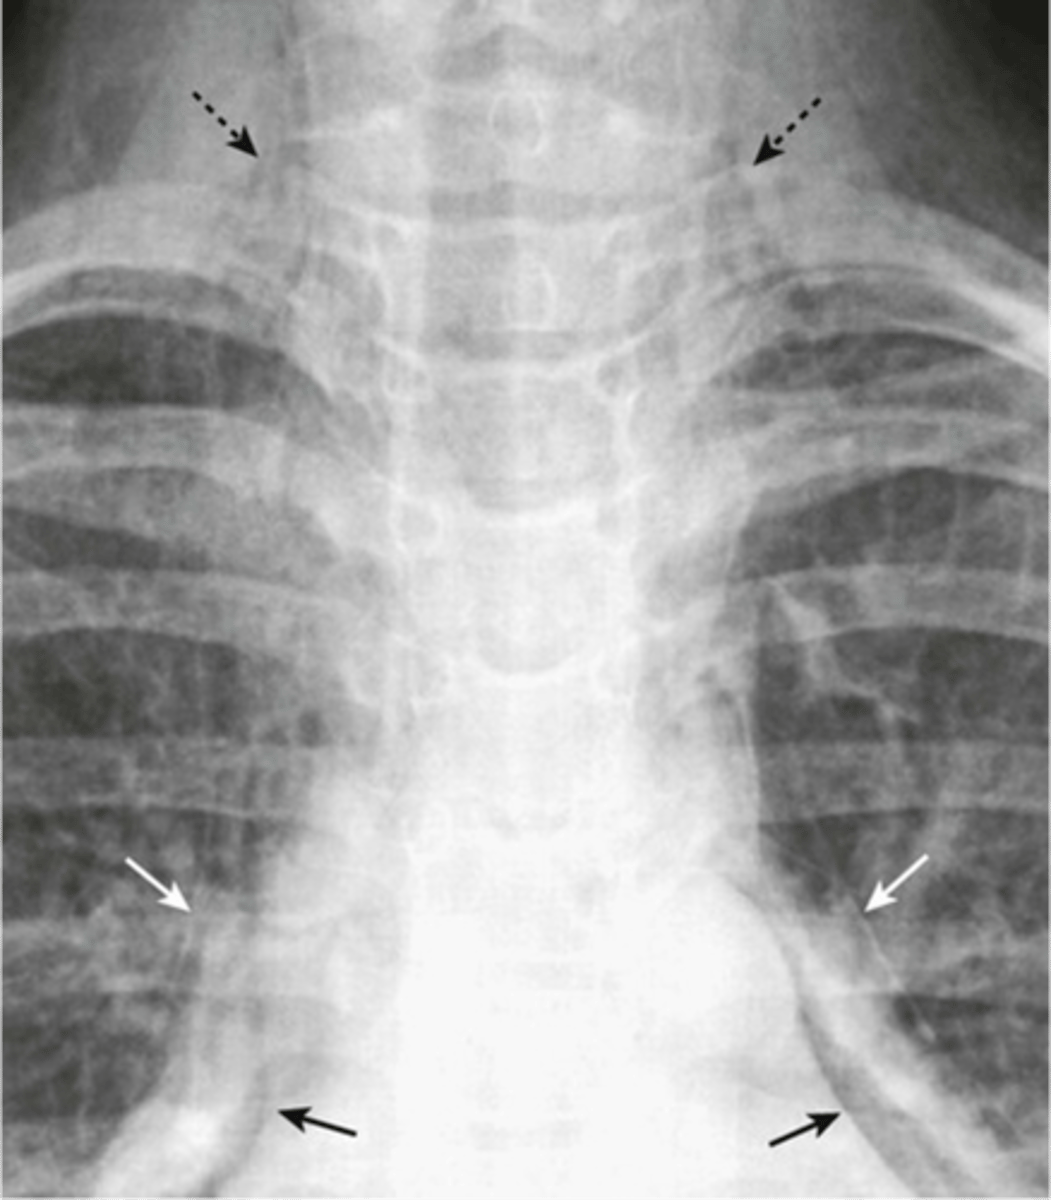

-stringy densities (air in neck)

-air around the heart

Pneumomediastinum appearance

very thick white line on the subcutaneous area

subcutaneous emphysema appearance